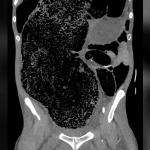

Случаят с Хилиърд обаче е специален, тъй като нейната хипотермия е била наистина екстремна. Оставете настрана, че температурата на тялото ѝ е била едва 27 градуса по Целзий – 10 под нормата за здрав човек. Тя, очевидно, е била замръзнала. Нейното лице е било бледо, очите – неподвижни, а кожата – прекалено твърда, че да бъде пробита от хиподермична игла.

„Тялото беше студено, напълно твърдо, досущ като дълбоко замразено парче месо“, казва Джордж Сатър, един от лекарите, които я връщат към живот.